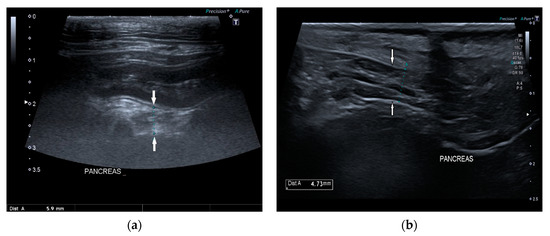

In 15/22 dogs (68%), the pancreas had a normal ultrasound appearance, with normal shape, margins, and echogenicity, homogeneous echotexture, and without pancreatic duct abnormalities (Figure 2).

Figure 2.

Ultrasound image of the right pancreatic limb with normal shape and echogenicity, regular margin, and homogeneous echotexture.